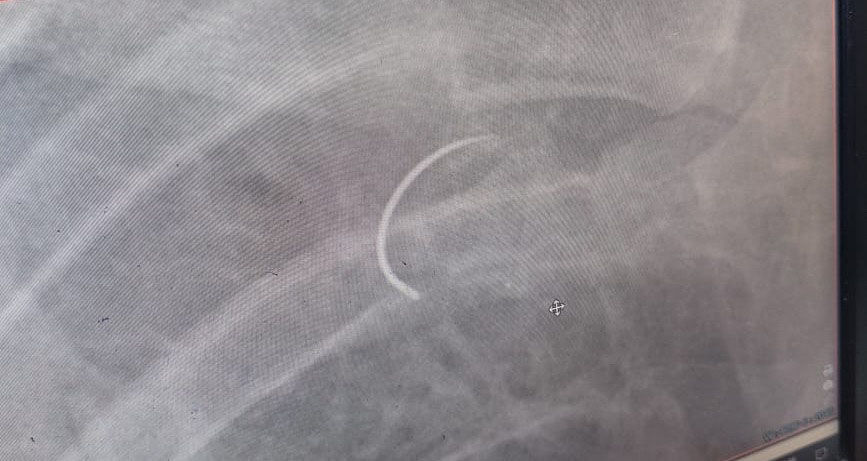

- Мне было тяжело дышать. Врачи посоветовали дуть в шарики, чтобы укрепить легкие. Позже сделали новый рентген, вот тогда на новом снимке обнаружили - в легком застряла игла, - рассказывает Сагин.

Ситуация потребовала срочной повторной операции. Хирурги извлекли инородный предмет и промыли плевральную полость, где скопилась жидкость.